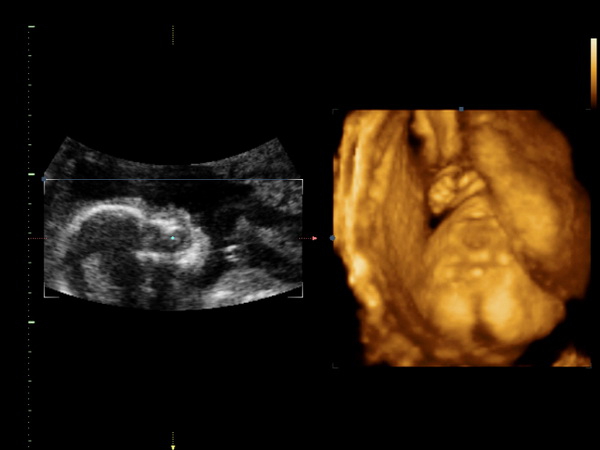

Kép